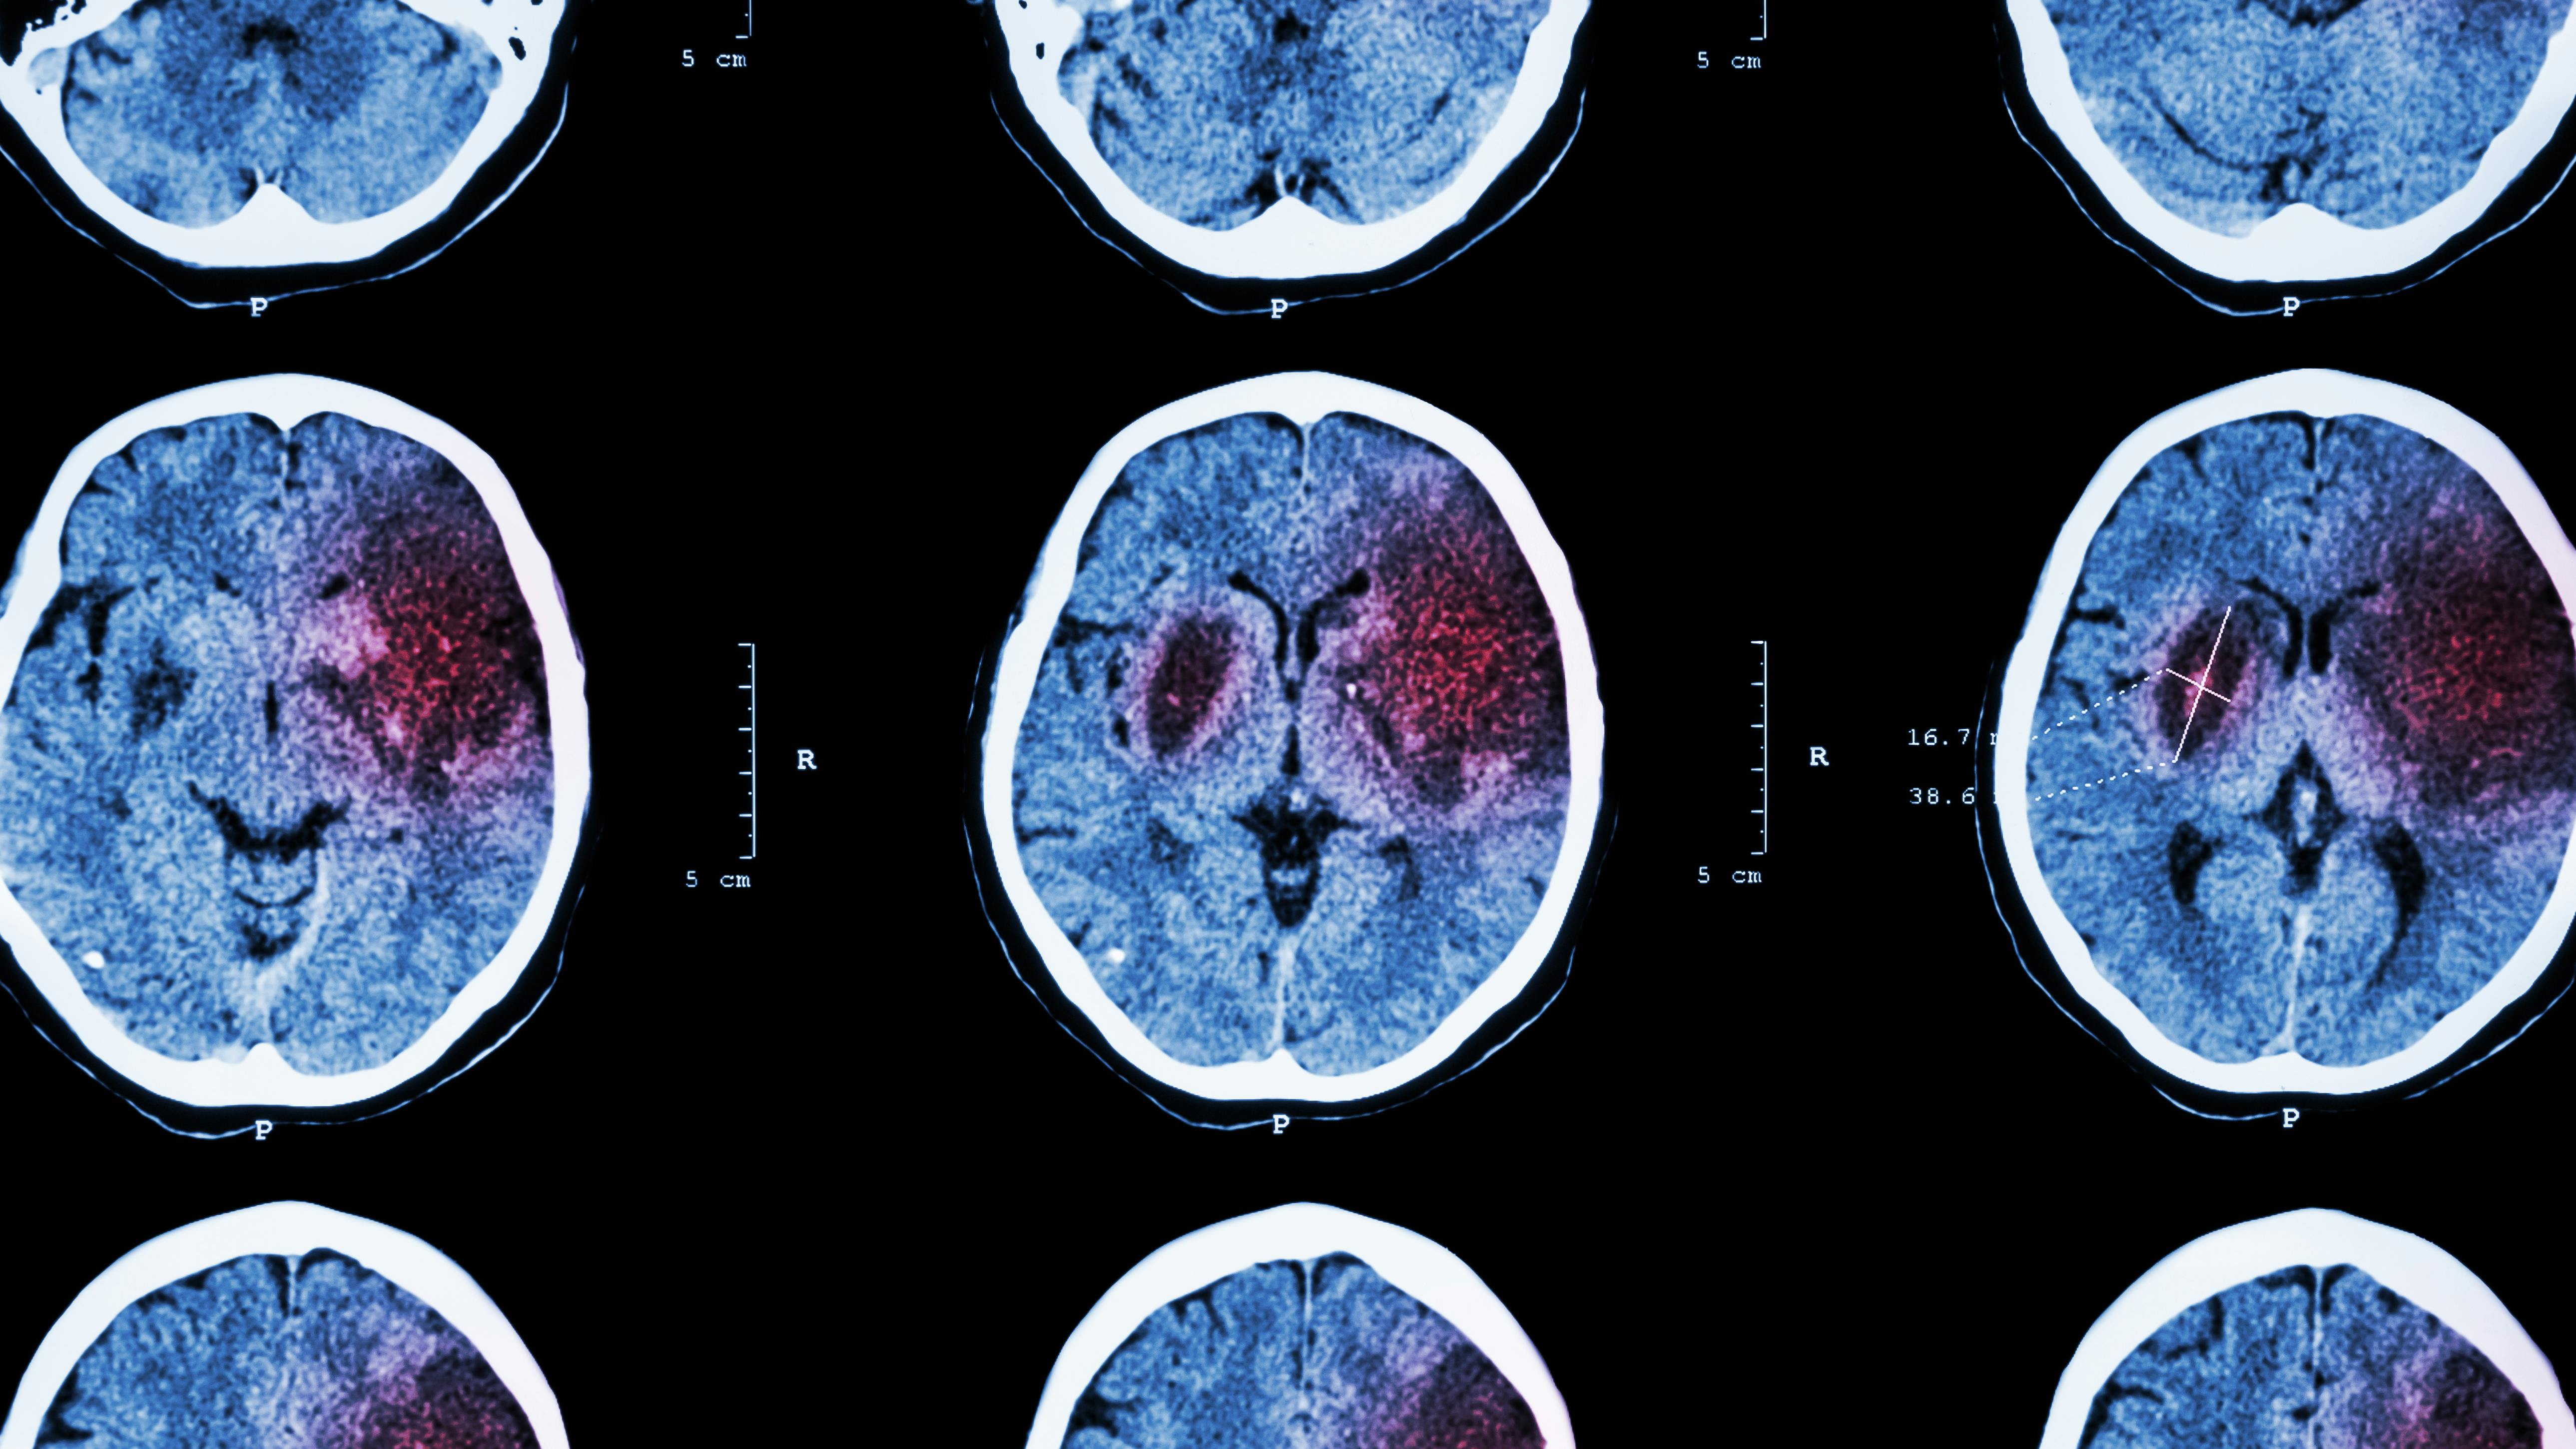

High blood pressure is a common condition where the force of blood against the artery walls is consistently too high, typically defined as a reading of 130/80 mmHg or higher.1 According to the World Health Organization, the number of adults aged 30–79 with hypertension has doubled in the past 30 years, reaching 1.28 billion globally.2

So, what can be done to combat this “silent killer,” a major risk factor for heart disease, stroke, and kidney damage? High blood pressure often shows no symptoms until severe complications arise, making prevention vital.

Oral infections contribute to high blood pressure through several mechanisms. They can cause chronic low-grade inflammation, which stiffens arteries and raises blood pressure. Bacteria from infected gums can also enter the bloodstream during daily activities such as chewing or brushing. Once in the bloodstream, they can adhere to artery walls, causing plaque buildup, narrowing blood vessels (vasoconstriction), and further elevating blood pressure.

This inflammation also damages the endothelium, the thin lining of blood vessels, leading to vasoconstriction and increased resistance to blood flow. “This forces the heart to work harder, contributing to higher blood pressure.”